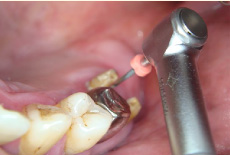

歯の根の治療は基本的な治療ですがとても複雑。

専用機器を使ったシステマチックな治療で効率良い処置を行っています。

- エンドシステム

- エンドシステム治療